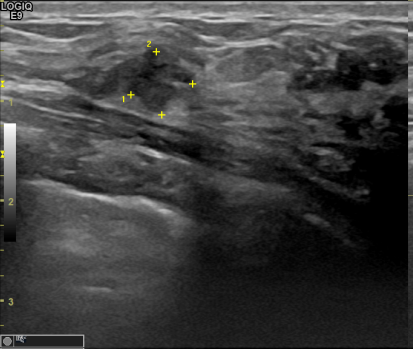

아산유외과개원후 770번째 유방암진단

상기환자 건진이상으로 내원하신 40대 여성분으로

우측 조직검사 시행해 침윤성암으로 진단되었습니다.